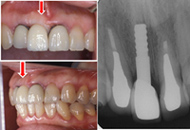

![]() 写真2■審美的な冠とは、歯を喪失する前のProfileに近づけること。すなわち、赤の外形線に近づけるには、歯肉縁下まで形成し、そこから歯冠を豊隆させる必要がある。 |

![]() 写真3■作業模型で見ると、天然歯に比べて、いかにインプラントの支台が細いかがわかる。冠のマージンからの豊隆度はこれ位が必要。 |

![]() 写真4■冠の装着時 両隣在天然歯の冠に近いEmergence Profile となっている。 |